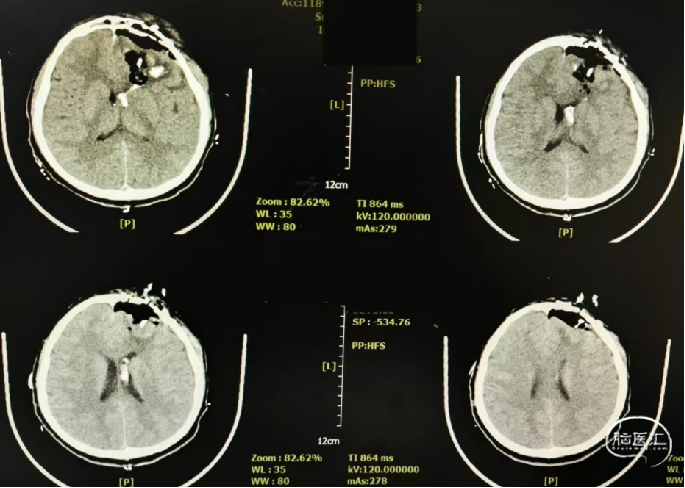

颅脑CT:左侧额叶脑出血,额部中线右侧移位约1.1cm,出血量约64ml,破入左侧侧脑室。额骨、蝶骨、鼻骨、筛骨、左侧上颌骨及左眼眶壁粉碎性骨折,全组鼻窦积血。

诊断:1. 左侧额叶创伤性脑内血肿。2. 左侧额部创伤性硬膜外血肿。3. 额叶多发脑挫裂伤。4. 创伤性脑室内出血。5. 额骨、蝶骨、鼻骨、筛骨、上颌骨、眶骨粉碎性骨折。

术前CT